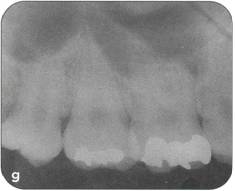

Fi 545e45f gs 5-2p and 5-2q Two years 5 months after transplantation. The donor tooth is restored with composite resin. |

Restorative treatment Unnecessary tooth reduction can be avoided by careful restorative treatment planning (see Fi 545e45f gs 5-1, 5-4, and 5-6). Surgical procedure |